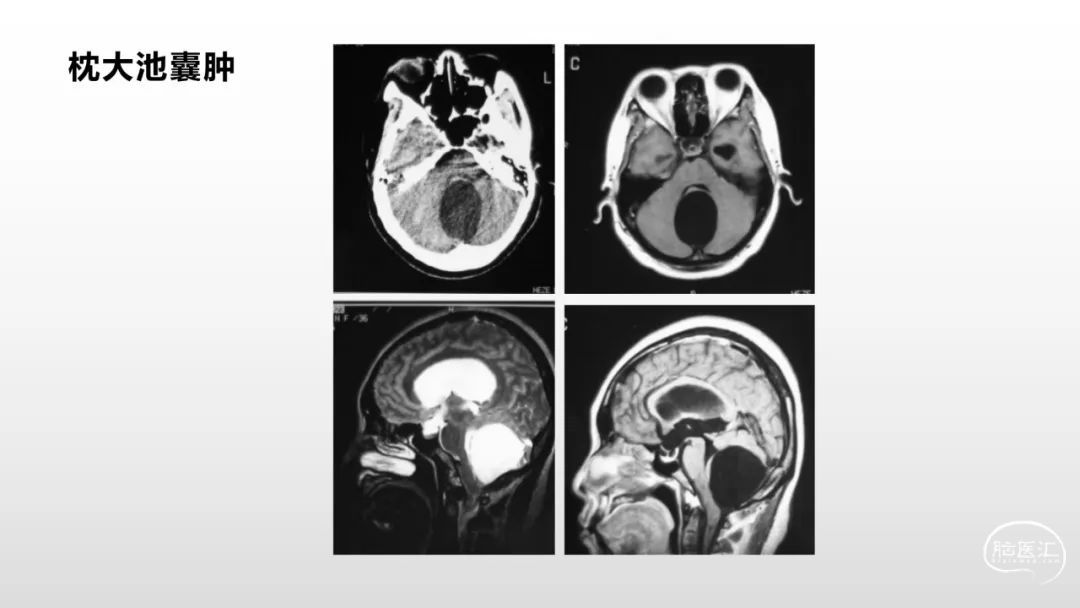

颅脑影像诊断基础知识讲座:脑膜病变